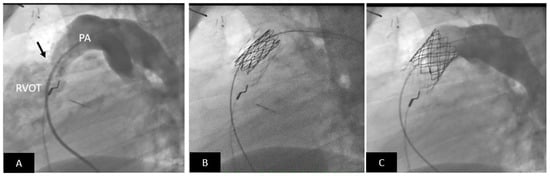

- Pluchinotta, F.R.; Sturla, F.; Caimi, A.; Giugno, L.; Chessa, M.; Giamberti, A.; Votta, E.; Redaelli, A.; Carminati, M. 3-Dimensional personalized planning for transcatheter pulmonary valve implantation in a dysfunctional right ventricular outflow tract. Int. J. Cardiol. 2020, 309, 33–39. [Google Scholar] [CrossRef]

2.3. Transcatheter Valve Therapies

- Bergersen, L.; Benson, L.N.; Gillespie, M.J.; Cheatham, S.L.; Crean, A.M.; Hor, K.N.; Horlick, E.M.; Lung, T.H.; McHenry, B.T.; Osten, M.D.; et al. Harmony Feasibility Trial: Acute and Short-Term Outcomes with a Self-Expanding Transcatheter Pulmonary Valve. JACC Cardiovasc. Interv. 2017, 10, 1763–1773. [Google Scholar] [CrossRef]